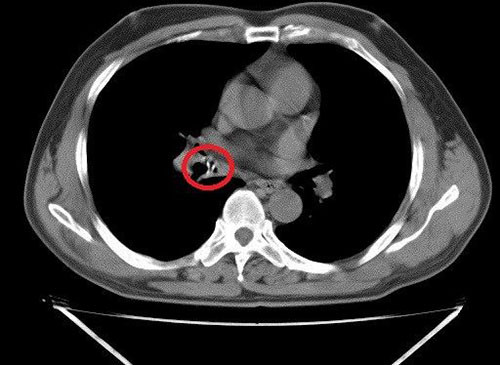

| Dị vật nằm trong phế quản của cụ ông khi nội soi. |

Ngày 28/5 ông Đính khó thở, đờm nhiều, gia đình đưa tới Bệnh viện Đa khoa Hà Tĩnh khám. Bác sĩ nội soi phát hiện dị vật dài 2 cm, rộng 1,5 cm nằm ở lòng phế quản trung gian phổi phải bệnh nhân.